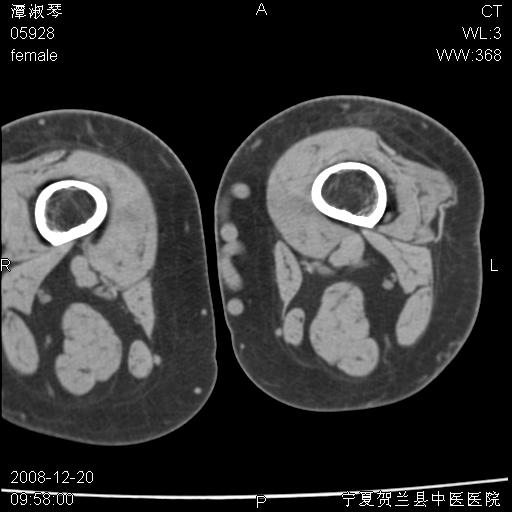

标题: CT17526:请各位看看是啥? [打印本页]

标题: CT17526:请各位看看是啥?

内生软骨瘤?骨梗死?

考虑内生软骨瘤可能性大

考虑-----骨梗死+退变

支持骨梗死,退行性骨关节病,膝关节积液.

支持骨纤或内生软骨瘤或骨梗死,退行性骨关节病,膝关节积液.

左股骨下段骨梗死。双膝退变。

支持:内生软骨瘤或骨梗死!另:退行性骨关节病,膝关节积液。

左胫骨下端松质骨及髓腔内可见点片状高密度灶,骨皮质无明显膨胀及变薄。病变范围较长。支持骨梗死,退行性骨关节病,膝关节积液